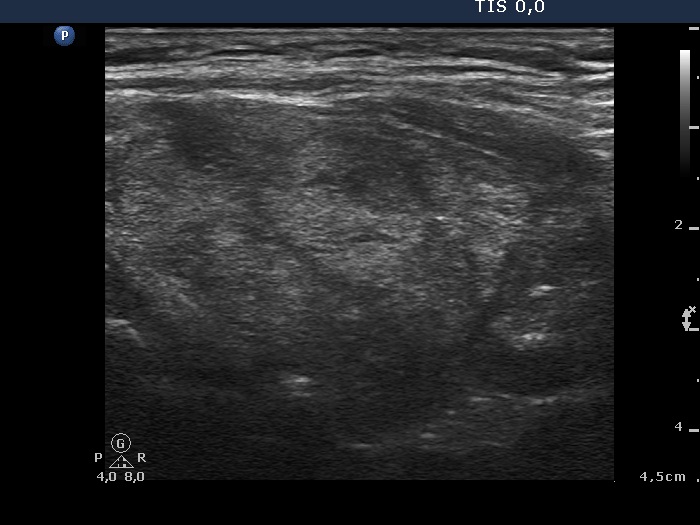

Case 1424 (ultrasonographic picture 5)

Left lobe, longitudinal scan. The upper nodular area is composed of multiple echonormal lesions while there is a hypoechogenic area in the lower part of the lobe.